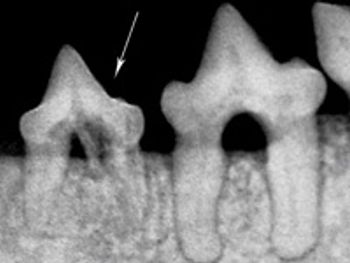

Two case examples display how radiography can reveal hidden pathology.

Correct management of periodontal patients in veterinary practice demands a thorough understanding of veterinary dental radiographic anatomy, periodontal probing and many times open evaluation and direct visualization of diseased areas. Stage III periodontal disease in particular requires advanced skills and familiarization with periodontal pathophysiology to make decisions to attempt to grow new supportive tissue adjacent to compromised teeth or extract them.